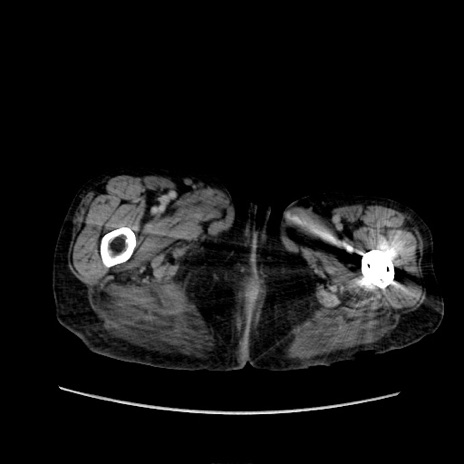

症例31(横断像)

【症例】80歳代 女性

【主訴】腹部膨満感

【現病歴】他院にて肝硬変にてフォロー中。1週間前から便秘、腹部膨満感、臍部腫瘤あり受診となる。

【既往歴】肝硬変

【身体所見】腹部膨隆あり、皮膚変化なし、疼痛なし。

【データ】WBC 4600、CRP 0.25